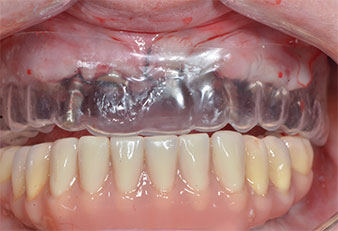

Поради сравнително твърдата кост (D2) в тази област, 10-милиметровото имплантно ложе в позиции 11 и 21 беше завършено с ротационен дрил с диаметър 4 mm в комбинация с W&H хирургичен обратен наконечник WS-75 L, W&H имплантологичен мотор Implantmed и опционалния W&H Osstell ISQ модул. За разлика от това, благодарение на меката кост, дисталните зони се подготвят до окончателен диаметър 3 mm, използвайки накрайник за Piezomed I3P. Имплантите най-накрая са поставени трансгингивално, за да остеоинтегрират за три месеца (Фиг. 6-10). Съществуващата протеза се фиксира на четирите временни импланта (Фиг. 8).